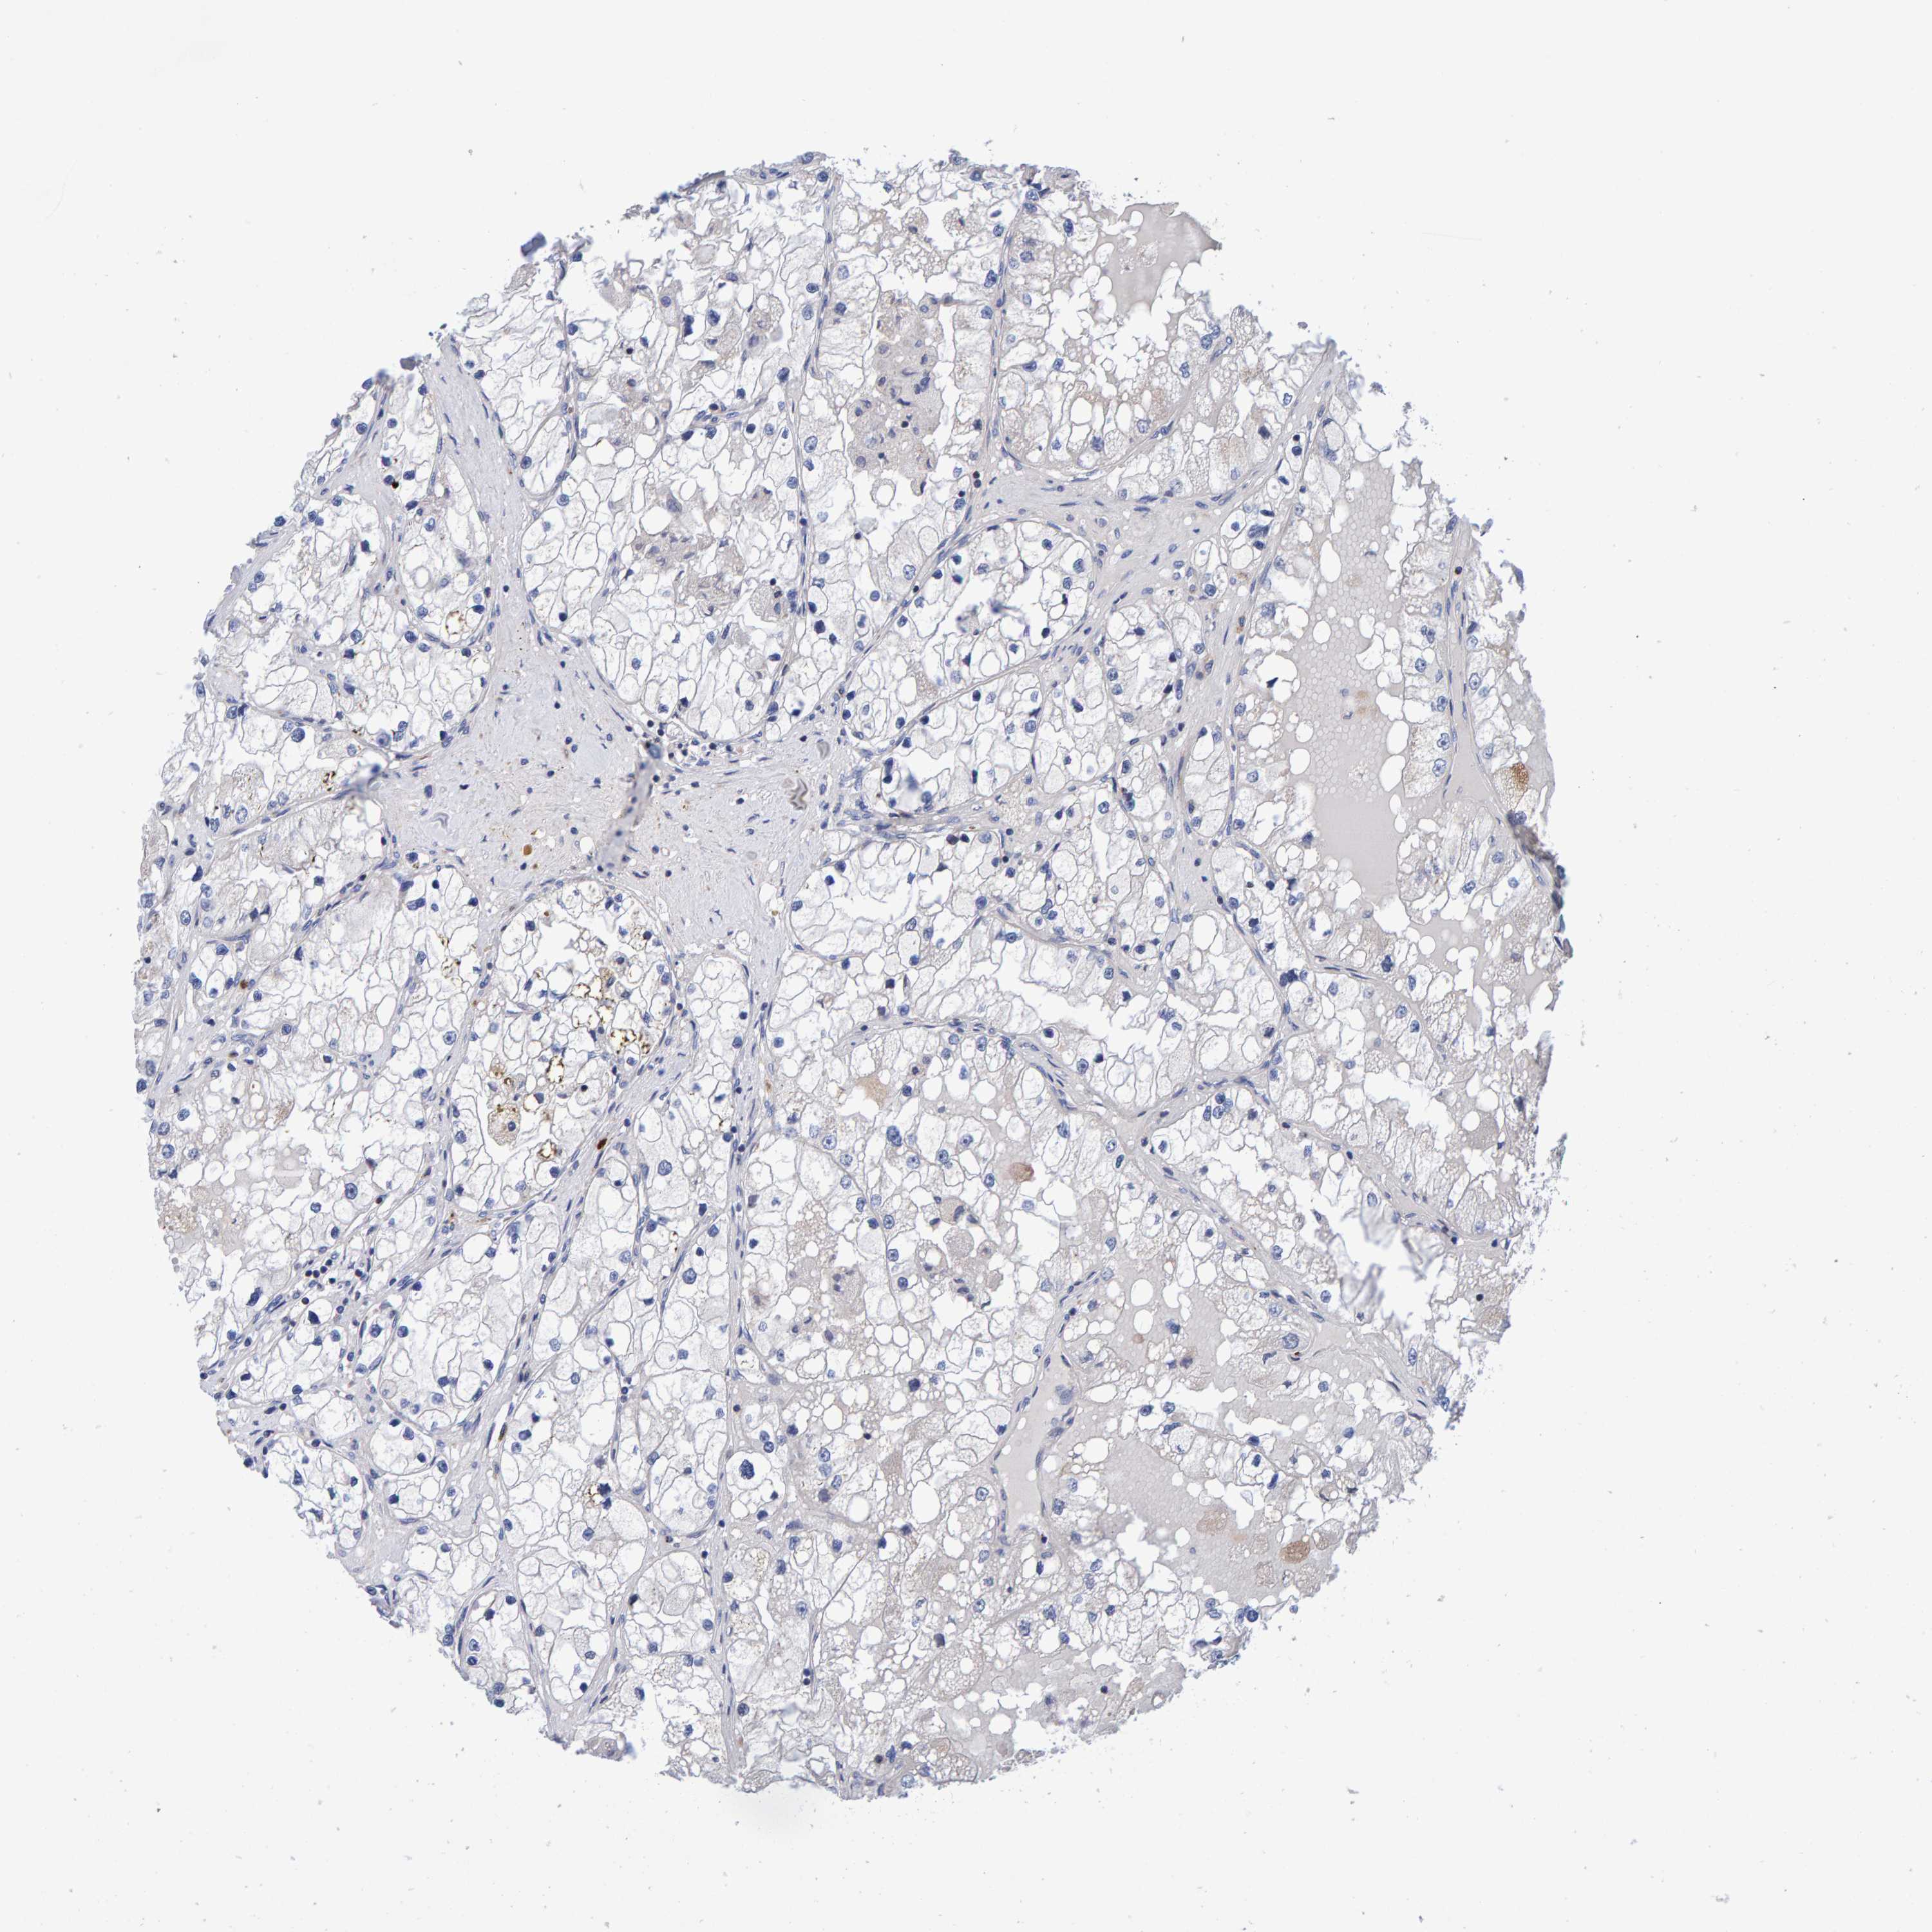

KIDNEY RENAL PAPILLARY CELL CARCINOMA (TCGA) - Interactive survival scatter ploti

The Survival Scatter plot shows the clinical status (i.e. dead or alive) for all individuals in the patient cohort, based on the same data that underlies the corresponding Kaplan-Meier plots. Patients that are alive at last time for follow-up are shown in blue and patients who have died during the study are shown in red.

The x-axis shows the expression levels (FPKM) of the investigated gene in the tumor tissue at the time of diagnosis. The y-axis shows the follow-up time after diagnosis (years). Both axes are complimented with kernel density curves demonstrating the data density over the axes. The top density plot shows the expression levels (FPKM) distribution among dead (red) and alive patients (blue). The right density plot shows the data density of the survived years of dead patients with high and low expression levels respectively, stratified using the cutoff indicated by the vertical dashed line through the Survival Scatter plot. This cutoff is automatically defined based on the FPKM cutoff that minimizes the p-score. The cutoff can be changed by dragging the vertical line or by entering a cutoff value in the square labeled "Current cut-off".

Under the Survival Scatter plot the p-score landscape (black curve; left axis) is shown together with dead median separation (red curve; right axis). Dead median separation is the difference in median mRNA expression between patients who have died with high and low expression, respectively. It is calculated as follows: median FPKM expression of dead patients with high expression - median FPKM expression of dead patients with low expression. This is intended to aid the user in visually exploring custom cutoffs and the associated p-scores and dead median separation.

Individual patient data is displayed and can be filtered by clicking on one or more of the category buttons on the top of the page. Categories describing expression level and patient information include: high, low, alive, dead, female, male and tumor stages. The scale of the x-axis can be toggled between linear and log-scale by clicking on the "x log" button. Mouse-over function shows TCGA ID, patient information and mRNA expression (FPKM) for each patient.

& Survival analysisi

Kaplan-Meier plots summarize results from analysis of correlation between mRNA expression level and patient survival. Patients were divided based on level of expression into one of the two groups "low" (under cut off) or "high" (over cut off). X-axis shows time for survival (years) and y-axis shows the probability of survival, where 1.0 corresponds to 100 percent.

EFR3A is not prognostic in Kidney Renal Papillary Cell Carcinoma (TCGA)